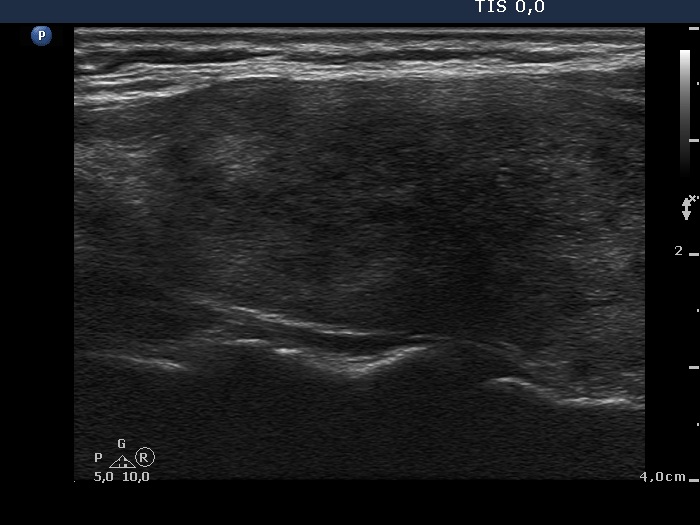

Subacute granulomatous de Quervain's thyroiditis - Case 6. (ultrasonographic picture 2)

Right lobe, longitudinal scan.